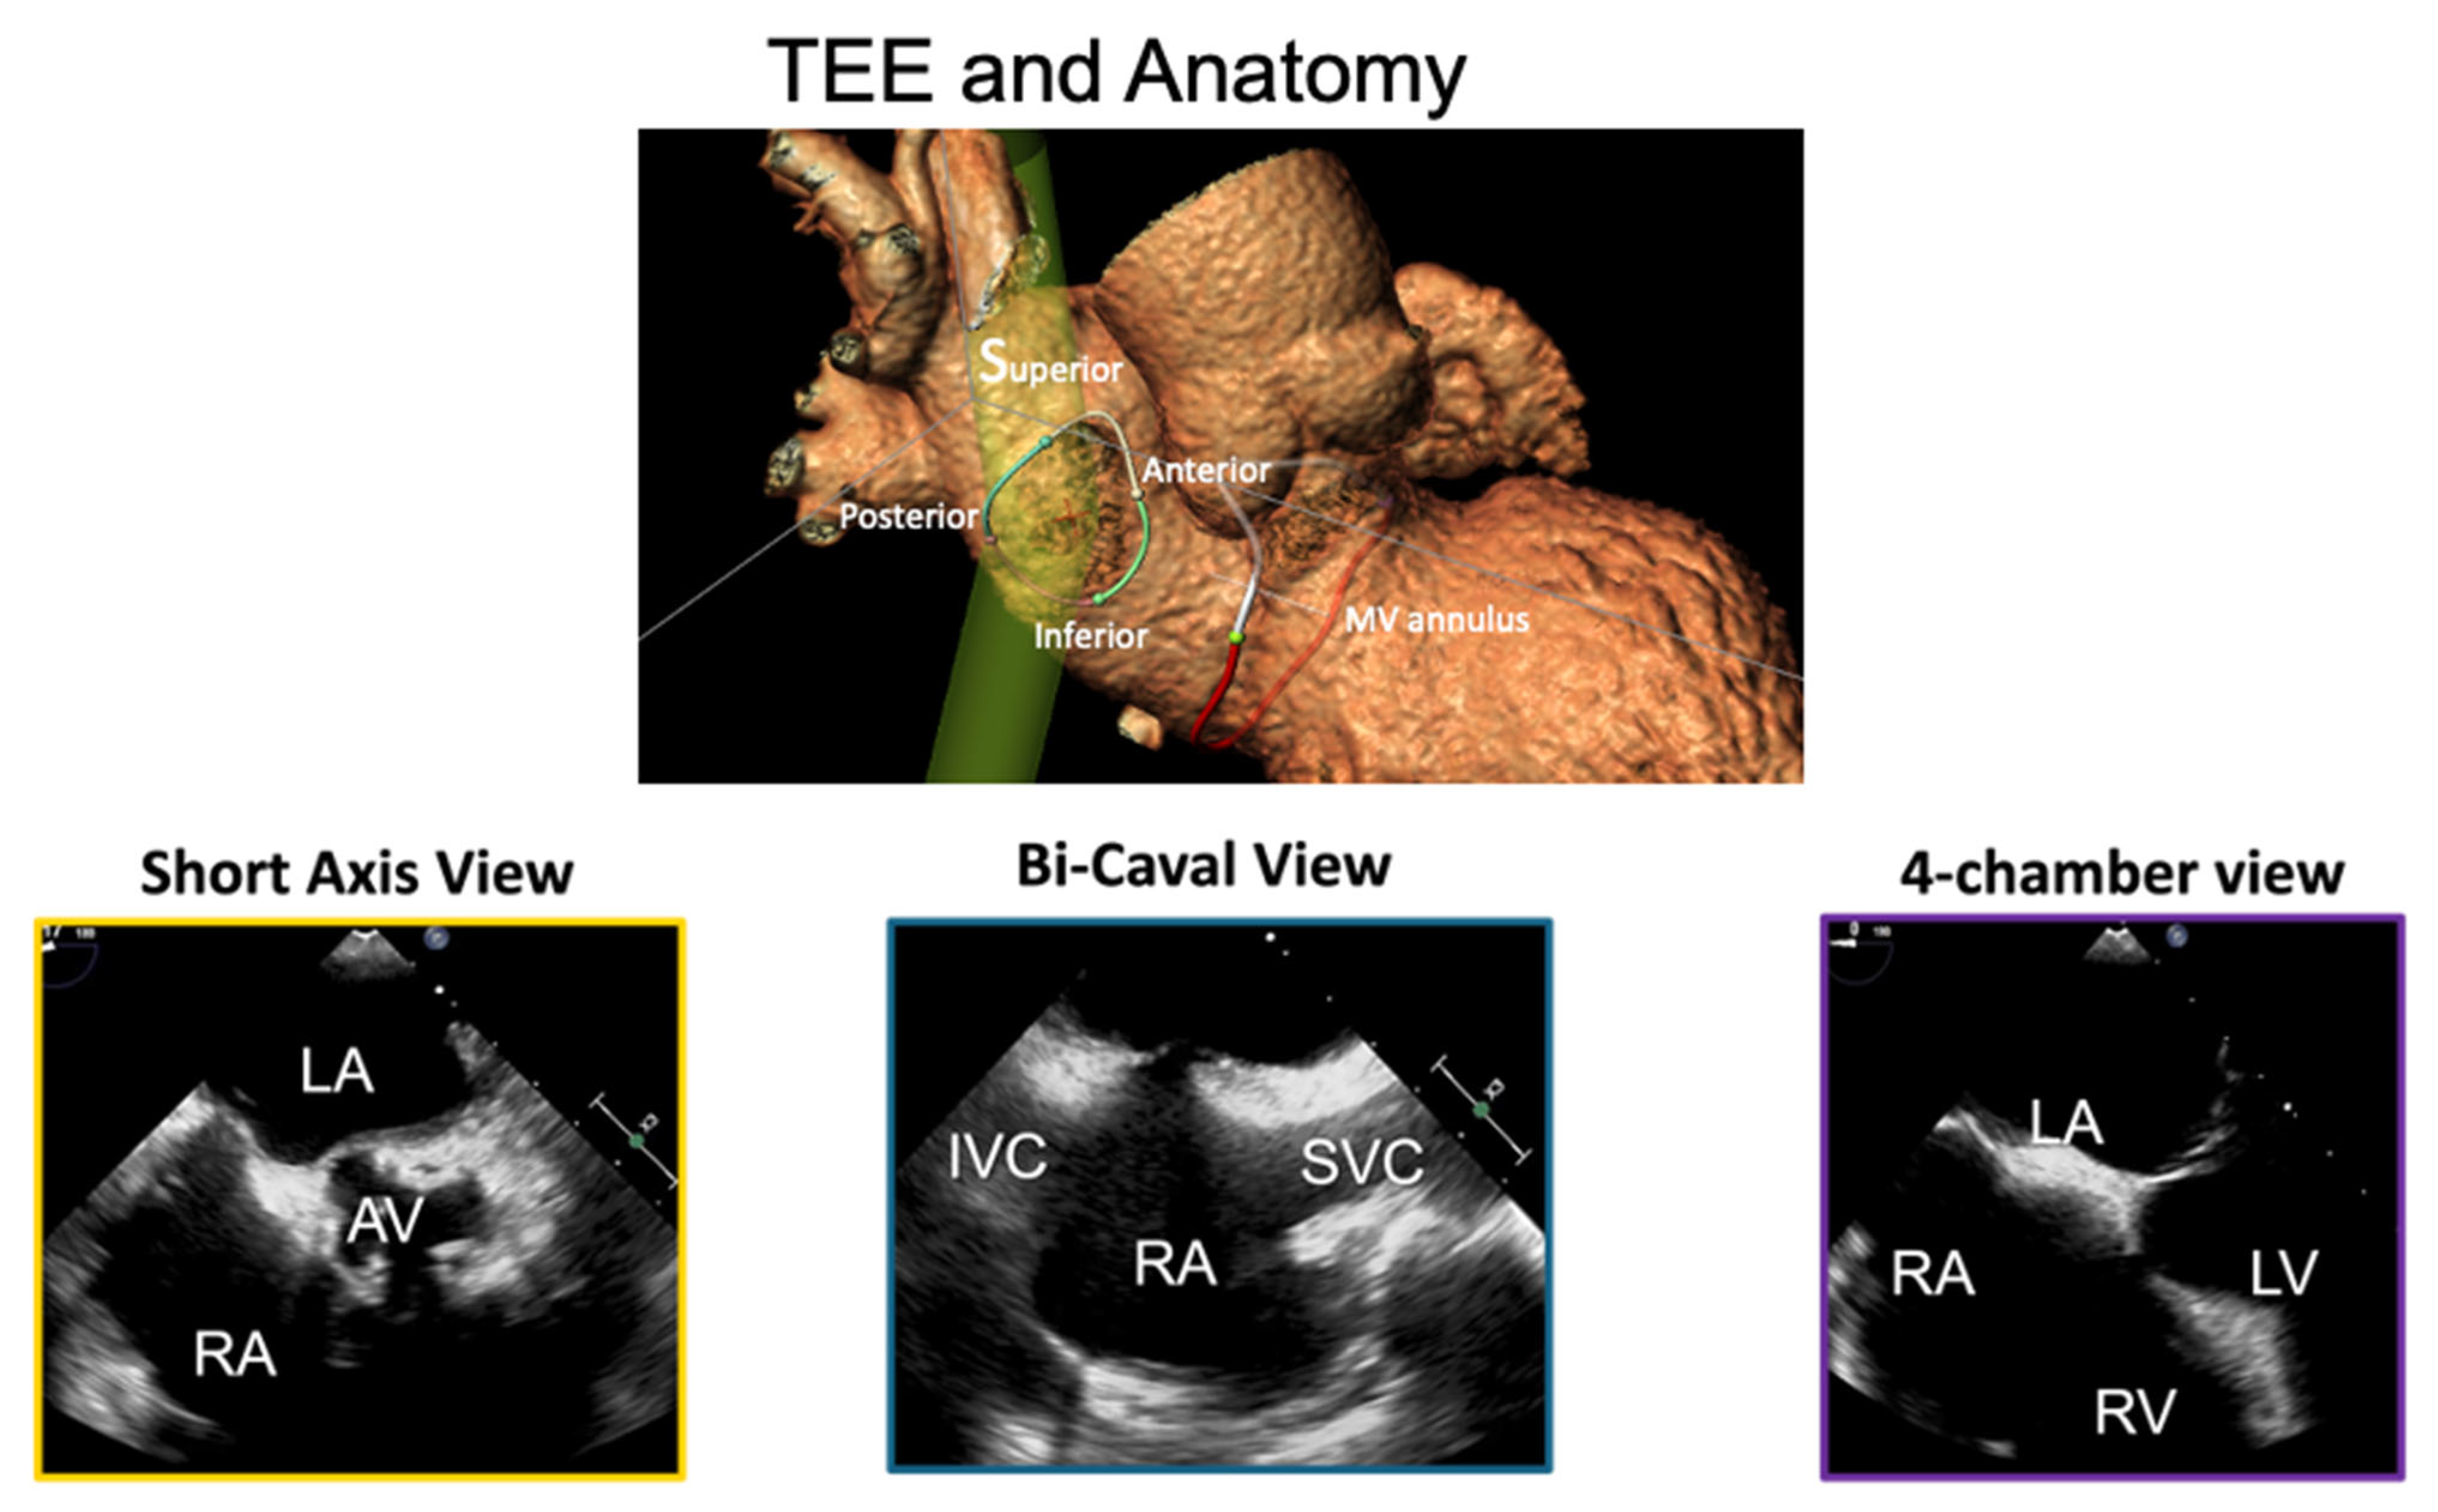

Figure 1. This approach enables the use of larger devices with improved maneuverability compared to retrograde arterial cannulation.

A 0.0032 guidewire is advanced in the superior vena cava. A 12F introducer sheath can be used, but in echo-guided TSP, it is not mandatory, since no tactile feedback will be needed to confirm septal engagement. The transseptal sheath and dilator are advanced over the guidewire to reach the superior vena cava (SVC) under fluoroscopic (AP projection) and TEE (bicaval view) guidance, as shown in

Figure 1. For cases involving pacemaker electrodes, to position the guidewire posterior to the leads, the advancement of the guidewire is performed in the LAO projection. When advancing the sheath, the tip is aimed leftward (toward the aorta) to avoid the cava free wall.

Then, a “pull-back” maneuver begins with the needle arrow pointing at 5 or 6 o’clock. For posterior punctures, the arrow is maintained at 6 o’clock. It is then pulled back caudally until the needle tents the superior rim of the fossa, observed via TEE, as shown in

Figure 2. Proper tenting is typically accompanied by supraventricular extrasystolic beats. Pulling the device back a few more centimeters will result in the needle falling in the fossa. Optimal puncture locations depend on the type of procedure, device used, and anatomy.

Using TEE (SAX view) and fluoroscopy (AP projection), the needle punctures the fossa ovalis, verified by a loss of tenting on TEE and left atrial pressure confirmation. Advancing the sheath should be avoided without proper pressure tracing or if aortic pressure is detected. In experienced hands, pressure monitoring can be avoided in TEE-guided procedures, however, pressure tracing enables greater safety. Full heparinization (100 U/kg) should be administered to maintain an activated clotting time (ACT) of 250–300 s.